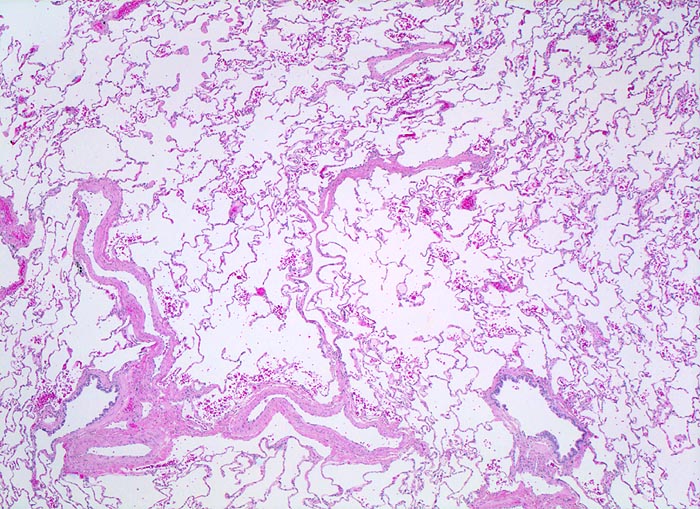

• In den sternförmigen Ausläufern finden sich erweiterte Endothelausgekleidete Lymphgefässe in der Nachbarschaft von Blutgefässen.

• Die erweiterten Lymphgefässe enthalten solide Tumorzellaggregate.

• Vermehrte Alveolarmakrophagen in den peritumoralen Alveolen mit phagozytiertem Anthrakose- und Hämosiderinpigment (Rauchermakrophagen).

• Peritumorales Lungenemphysem (Traktionsemphysem).